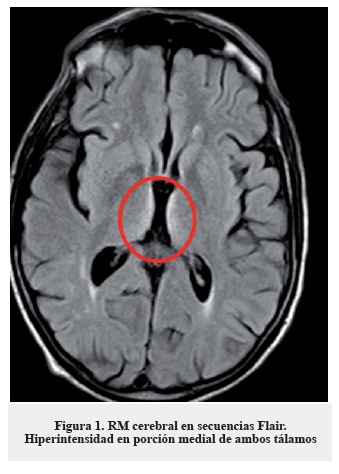

La clínica, los hallazgos en la exploración neurológica y el antecedente de cirugía resectiva gastrointestinal hacen sospechar como primera posibilidad diagnóstica una encefalopatía de Wernicke, probablemente desencadenada en el contexto de vómitos y administración de suero glucosado. Dada la alta morbimortalidad del cuadro se inició de forma urgente tratamiento sustitutivo con tiamina (vitamina B1) 300 mg intramuscular, asociada a cianocobalamina (vitamina B12) y piridoxina (vitamina B6) parenterales. No se pudo realizar determinación de niveles séricos de vitamina B1 previa a la administración del tratamiento de reposición. El tratamiento se instauró de forma diaria durante diez días, objetivando una mejoría sintomática a las veinticuatro horas tras la primera dosis, progresiva. Como única prueba complementaria se solicitó un estudio de neuroimagen con RM cerebral (secuencias habituales, difusión y secuencias dinámicas tras la administración de contraste intravenoso (gadolinio)) en la que se apreció hiperseñal simétrica en secuencias T2 y Flair de la porción medial de ambos tálamos (Figura 1), cuerpos mamilares y sustancia gris periacueductal (Figura 2), que se acompaña de una restricción de la difusión en la porción medial de ambos tálamos (Figura 3); además se evidenció hiposeñal simétrica y bilateral de ambos núcleos pálidos; todo ello compatible con encefalopatía de Wernicke.

Se señalan en las imágenes dichos hallazgos. Los hallazgos de resonancia magnética, si bien son poco sensibles (53%), son altamente específicos (93%), e incluso se señalan como patognomónicos en algunos manuales/artículos publicados, por lo que el diagnóstico diferencial no se establece con base en estos hallazgos. No es posible recoger imágenes de mayor resolución, pues estas han sido obtenidas directamente del programa utilizado por los radiólogos del hospital.